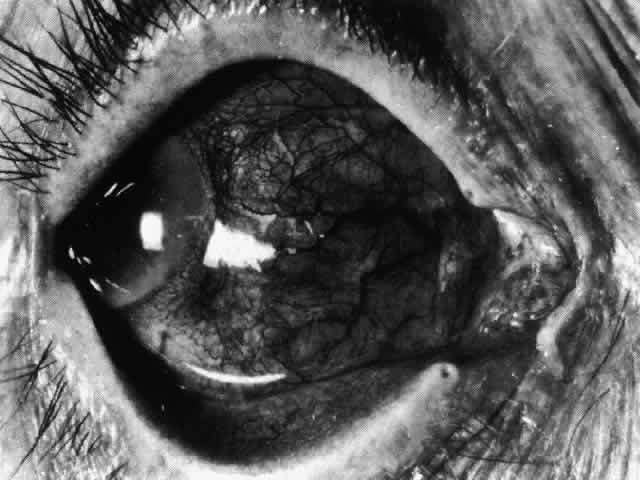

Necrotizing Anterior ScleritisdWithout Adjacent Inflammationd(Scleromalacia Perforans) Necrotizing anterior scleritis without adjacent inflammation appears to be a well-defined condition with little relation in clinical features to necrotizing scleral disease, even though the pathology is similar and the final result is the same. Scleromalacia perforans is characterized by the almost total lack of any symptoms. It occurs almost exclusively in patients with long-standing polyarticular rheumatoid arthritis, the majority of whom are female (Figs. 49 and 50; Color Plate 1E).

The anterior sclera loses its covering of episclera and develops an area of yellow-white necrotic slough over many months; this eventually separates or is absorbed, leaving the underlying choroid covered by either conjunctiva or nothing at all. As with necrotizing disease, the choroid does not bulge into this ectatic area; but unlike necrotizing disease, spontaneous healing of even small perforations is very limited once the necrotic tissue has been removed (see Fig. 50). Fluorescein angiography is not helpful, except to indicate areas of vascular closure in an otherwise extremely thin, atrophic episcleral tissue.4 The formation of a sequestrum appears to be caused by arteriolar closure as opposed to the venular disease seen in the other forms of necrotizing scleritis. Posterior Scleritis Because the posterior sclera is invisible, the diagnosis of posterior scleritis is made only if the anterior sclera is also involved or some other sign or symptom leads one to suspect it. Posterior scleritis is much more common than previously suspected, as recent clinical and pathologic studies have shown.19,28,29 There are two distinct forms of posterior scleritis. The first is usually associated with an anterior scleritis. This granulomatous disorder, like its anterior counterpart, can be diffuse, nodular, or necrotizing in character and is associated with the connective tissue diseases. The second form occurs in young patients of all races who are 9 to 40 years of age. It is always diffuse in character but is not associated with any systemic disorder. Both forms may cause uveitis if the inflammation affects the ciliary body, and in both forms the patient may develop exudative retinal detachments, choroidal folds, and swelling of the disc (Figs. 51 and 52). The granulomatous type may also involve the structures outside the globe, causing proptosis (Fig. 53), limitation of ocular muscle movement, and, uniquely, retraction of the lower lid on attempted elevation of the eye (Fig. 54). Diagnosis is with B-scan ultrasonography. TREATMENT Scleritis is almost always accompanied by very severe pain that prevents sleep. A response to treatment is heralded by a dramatic relief of pain even though the condition might appear to be getting worse (Figs. 55 through 59). Treatment may be modified with confidence once the pain has disappeared.